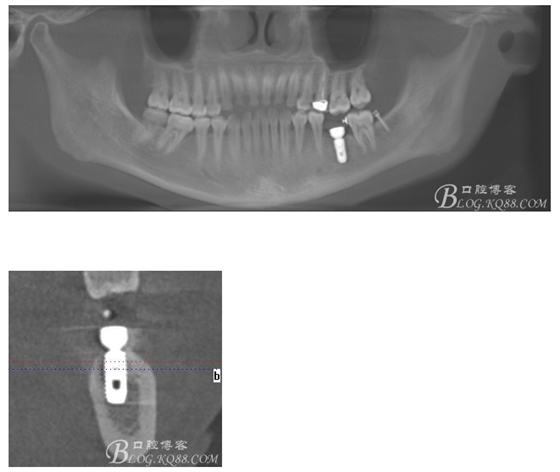

檢查:36.46缺失,36缺牙區(qū)近遠(yuǎn)中間隙約3mm,46缺牙區(qū)間隙約0.5mm,37.47.48近中傾斜,48近中面齲壞達(dá)牙本質(zhì)淺層,37牙周探診4mm,47近中探診深度5-6mm,不松,口內(nèi)照片及CT片如下:

術(shù)前CT

植入5.0X10mm植體

術(shù)后CT片